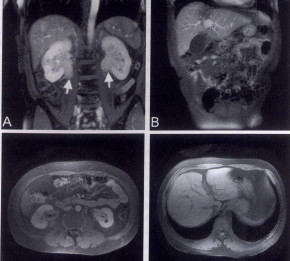

Treatment of hyper-IgG4 disease with sequential corticosteroids and tamoxifen

Credits

Dr. K. Feistle - 2009